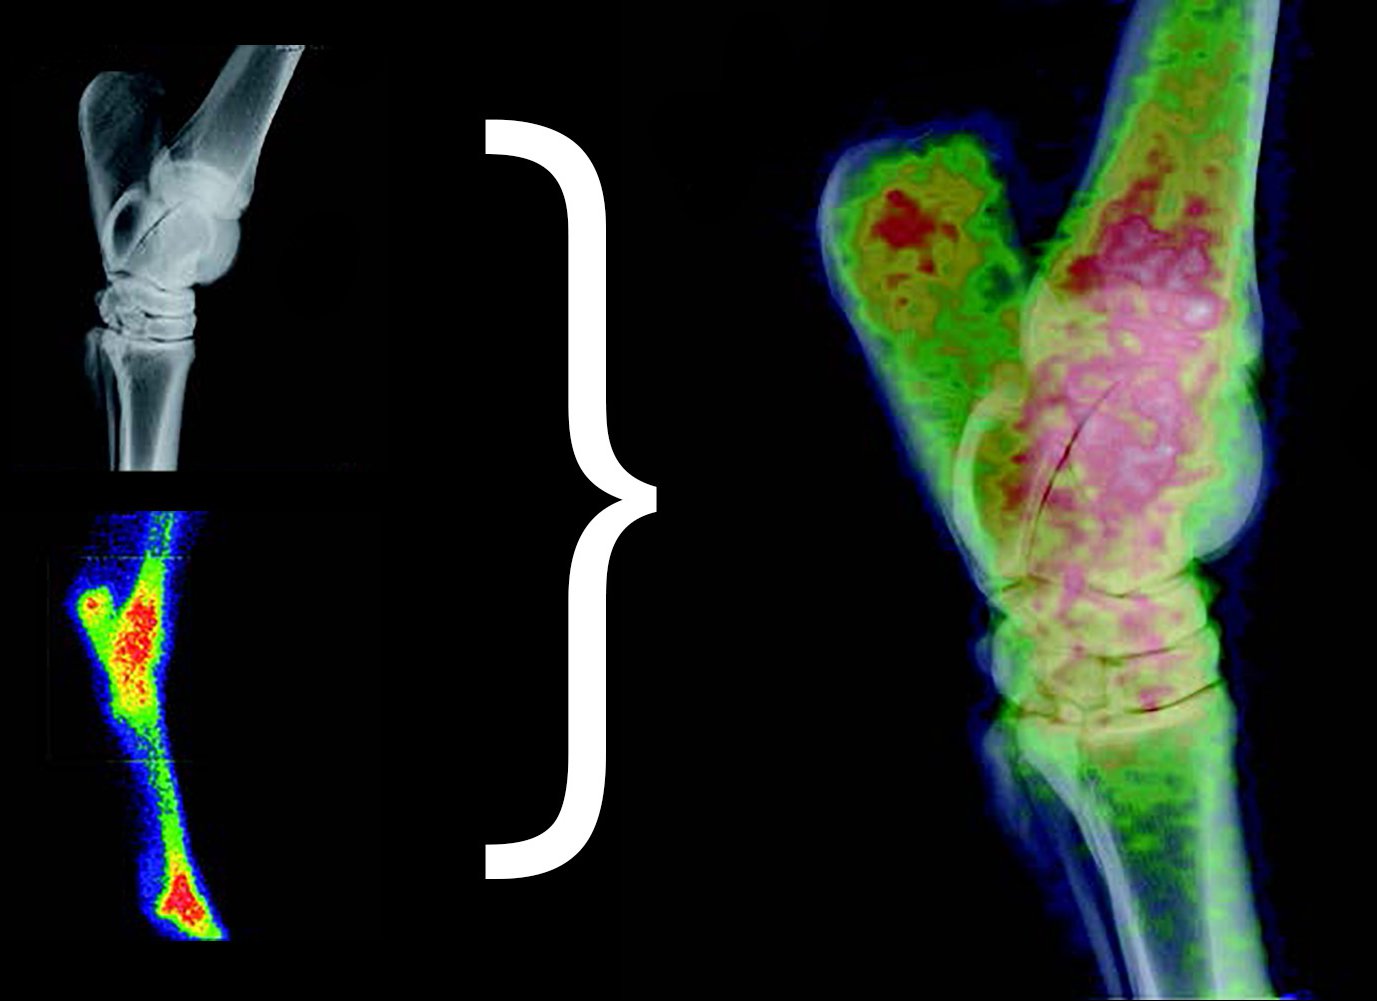

IMAGE FUSION

MiE’s Image Fusion for scintigraphy and x-ray images enhances the diagnostic possibilities. The program evaluates the different structures, resolution, acquisition geometries and regions. Rotation, translation (shift) and scaling will be adjusted.

The process operates multi modal and automatic. The fusion allows the combined usage of the morphologic information of the x-ray and the functional information of the scintigraphy in one image.